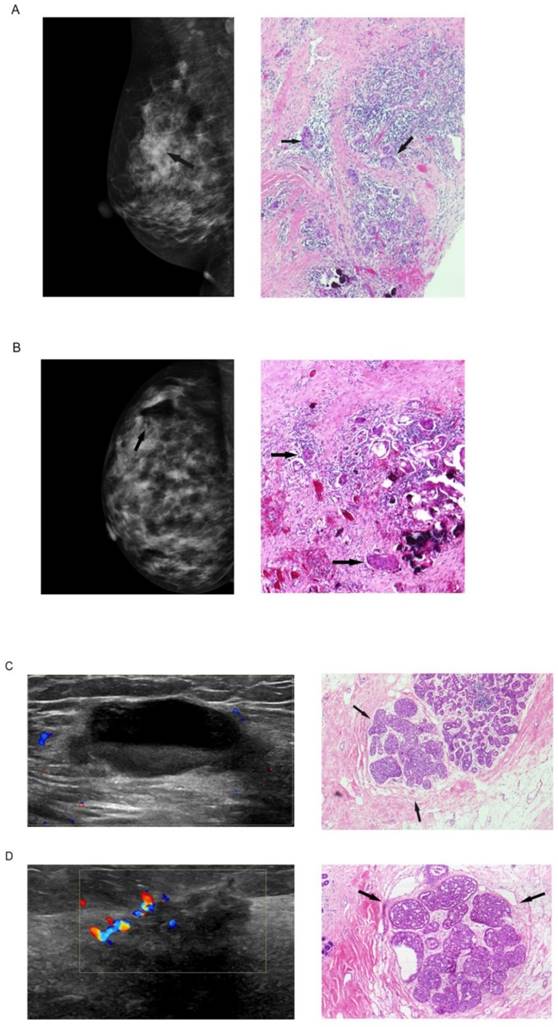

In total, 53 (42.1%) patients received mammogram and 115(91.3%) patients received ultrasound examination post VABB but before subsequent surgery (Table 4, Figure 1). Among these patients, 39 (76.5%) and 85 (73.9%) were estimated with no residual tumor by mammogram and ultrasound examinations, respectively. However, when compared with the histological findings, mammogram and ultrasound only had a sensitivity of 36.3% and 38.2%, which resulted in a negative predictive value of 46.2% and 50.6%. Namely, the probability for a patient free of histologically residual tumor was only 50% or even less when mammogram or ultrasound suggested no residual tumor after VABB. In addition, 12 (22.6%) patients were estimated with no residual tumor by mammogram and 26 (22.6%) by ultrasound, both with a high specificity of 90% or more, which resulted in a positive predictive value of 85.7% and 86.7%.

Figure 1

Mammogram and ultrasound findings post biopsy but before subsequent surgery and the corresponding histological findings: (A) mammogram finding suggested no residual tumor at the biopsy site of a 45-year-old woman, inconsistent with the final histological finding with residual tumor; (B) mammogram finding suggested residual tumor (residual microcalcification shown by arrow) of a 30-year-old woman, consistent with the final histological finding; (C) ultrasound finding suggested no residual tumor of a 35-year-old woman, inconsistent with the final histological finding; (D) ultrasound finding suggested residual tumor of a 35-year-old woman, consistent with the final histological finding.